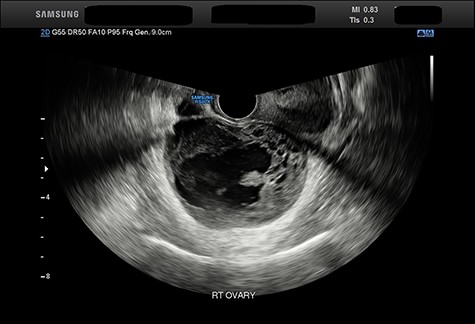

The pain settled somewhat and the patient contacted an Australian medical team for advice. The clinical picture suggested partial torsion of an ovarian cystic lesion and, due to the risk of a complete torsion and ovarian tumour infarction, advice was given to the Government that the patient be repatriated to Australia in view of the extreme pressure on medical resources where she was. However, the patient suffered another severe episode of pain suggestive of complete torsion and laparoscopy was undertaken. The images were captured on a phone camera and sent to Australia—the surgeons found a large cystic lesion apparently contiguous with the right ovary (Fig. 1) that was densely adherent to the small bowel and sigmoid colon. Further conservative management with analgesia was given and the patient was flown to Australia to undergo COVID-19 quarantine. She had an ongoing requirement for analgesics but no further acute episodes. Upon release from quarantine local ultrasound revealed a heterogeneous solid and cystic lesion of unchanged dimensions ‘strongly suggestive of primary ovarian neoplasia’ (Fig. 2). The remainder of the examination was normal Her CA-125 level was 15 kU/L (NR < 36).

Abdominal ultrasound imaging demonstrating a heterogeneous solid and cystic lesion 75 × 53 mm.